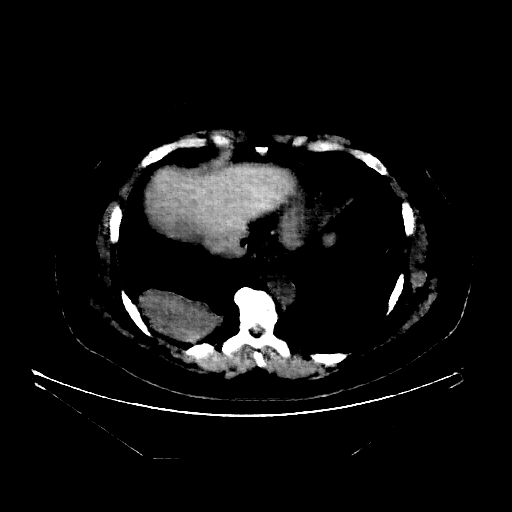

Generated VENOUS CT scan (A→B translation)

Full window (WL 1023.5, WW 4095 β†’ Low βˆ’1024, High +3071)

Actual HU range: [-1024.0, 897.0]

Lung window (WL -600, WW 1500 β†’ Low βˆ’1350, High +150)

Actual HU range: [-1162.5, 150.0]

Mediastinum window (WL 40, WW 400 β†’ Low βˆ’160, High +240)

Actual HU range: [-160.0, 240.0]